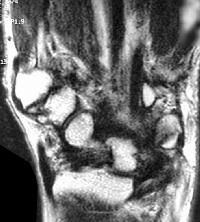

Mild wrist stiffness prevented adequate visualization of the hook of the hamate with plain films. Plain films of the finger were normal for age. Further evaluation was obtained with MRI. Flexor tendon signals in the finger were normal:

Sections through the carpal tunnel -  looking for a hook of hamate fracture or tendon discontinuity - were read as normal, although there may be a subtle signal irregularity through the hook of the hamate: